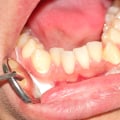

The bicuspids, also known as premolars, are important teeth located between the canines and molars. Understanding their anatomy is crucial to appreciating their functions in our oral cavity.

The structure of a bicuspid consists of two cusps, which are pointed or rounded elevations on the tooth's surface that aid in chewing food.

Bicuspids play a vital role in chewing and grinding food by providing support for the forceful movement of the jaw. Their unique shape allows them to break down tough foods into smaller particles before being swallowed. Moreover, they provide stability to adjacent teeth and maintain proper alignment of the dental arches.